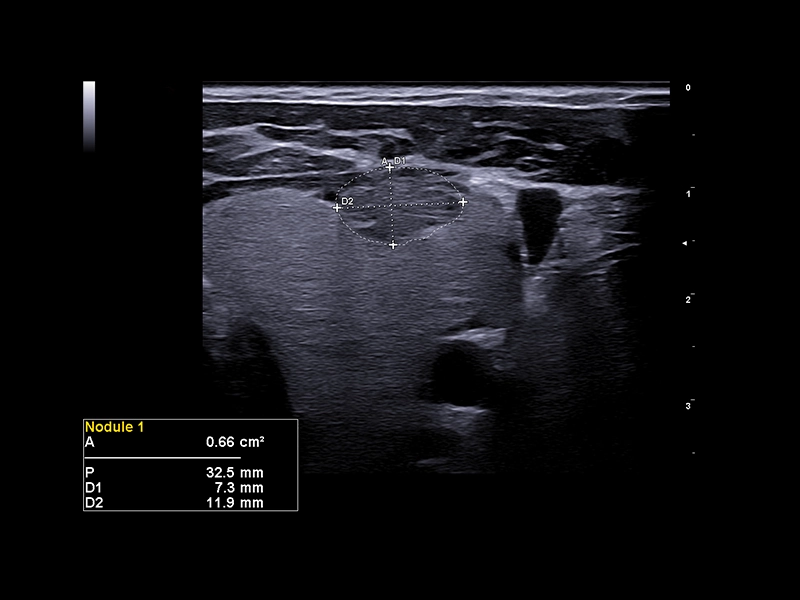

MyLab™X9 - Breast 01

MyLab™X9 - Breast 01